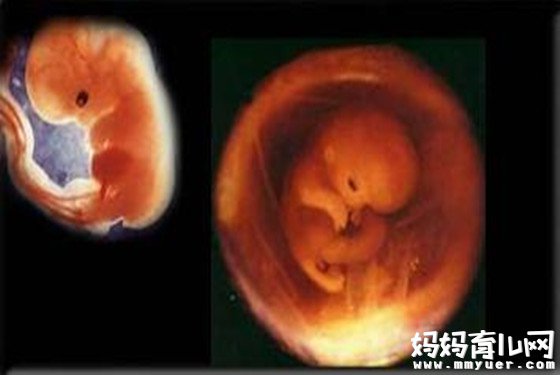

怀孕一个月胎儿图(详解)

孕3周:这一周受精卵经过3~4天的运动到达子宫腔,在这个过程中由一个细胞分裂成多个细胞,并成为一个总体积不变的实心细胞团,称为桑胚体。着床后,受精卵形似长了四个鳃、挂着长尾巴的鱼一样,并且身体、上头各占一半。此时胎儿仅仅为0.1厘米长,非常轻。

孕4周:怀孕第四周表示受精卵着床后,羊膜腔形成了。胎儿长度仅为0.2厘米,柔软且轻。此时的胎儿只有两层组织,之后他所有的器官、组织都靠这些组织发育形成。最初的胎盘细胞着床在子宫内膜上,开始为胎儿血液提供并制造空间。